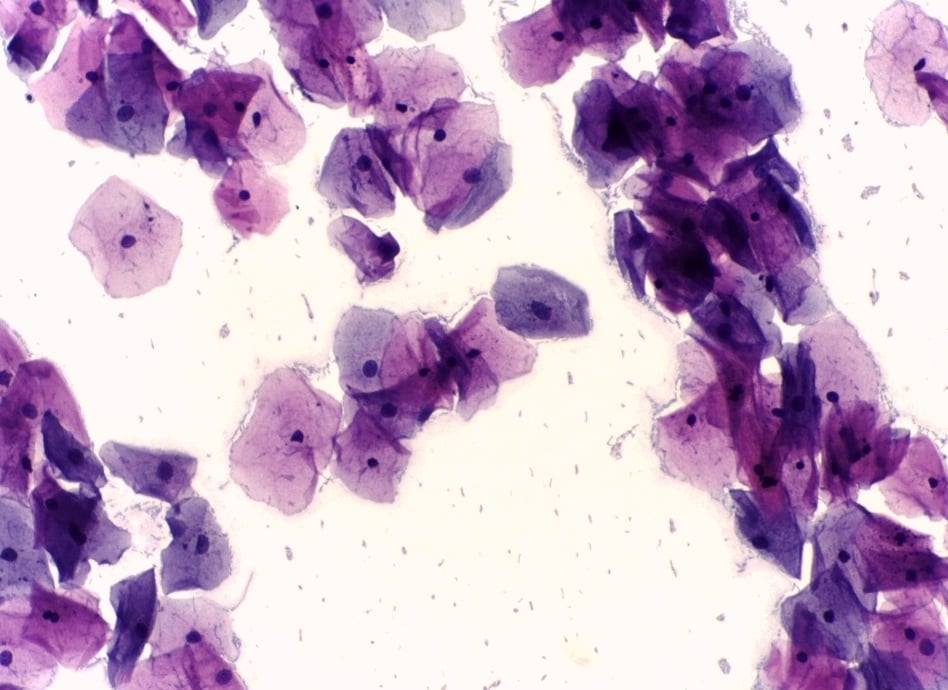

Kết quả Pap smear của một người phụ nữ. (Ảnh: Wikimedia)

Pap smear (xét nghiệm Papanicolaou) từng là phương pháp sàng lọc ung thư cổ tử cung đã được sử dụng rộng rãi từ giữa thế kỷ XX. Tuy nhiên trong những năm gần đây, một số quốc gia bắt đầu từ bỏ dần vai trò của xét nghiệm này.

Sự thay đổi này xuất phát từ khác biệt về nguyên lý giữa hai phương pháp. Pap smear là xét nghiệm tế bào học, đánh giá hình thái tế bào tại thời điểm lấy mẫu. Kết quả phụ thuộc vào chất lượng lấy mẫu, kỹ thuật xử lý và khả năng đọc lame của nhân viên y tế. Dù Pap smear nhúng dịch (liquid-based cytology) đã cải thiện phần nào độ đồng đều của mẫu, xét nghiệm này vẫn cần nhiều nhân lực được đào tạo và thời gian xử lý.